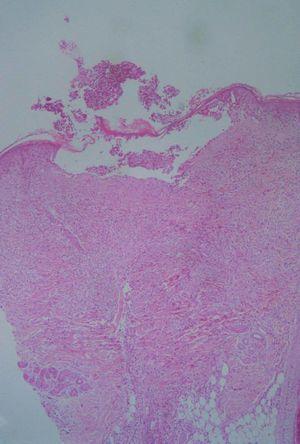

En el estudio histológico podía observarse un moderado infiltrado inflamatorio polimorfo compuesto por polimorfonucleares, eosinófilos y linfocitos, alrededor de los vasos y en el intersticio. Algunos de los folículos se encontraban densamente infiltrados por polimorfonucleares y eosinófilos, que destruían parcialmente la pared, ocupando el infundíbulo y afectando también la glándula sebácea (figs. 2 y 3). Se realizaron tinciones para la detección de estructuras micóticas (PAS y plata-metenamina) que resultaron negativas.

Fig. 2.--Imagen panorámica donde se observa en la epidermis una pústula subcórnea, acompañada de denso infiltrado inflamatorio que afecta a dermis e hipodermis. (Hematoxilina-eosina, x10.)